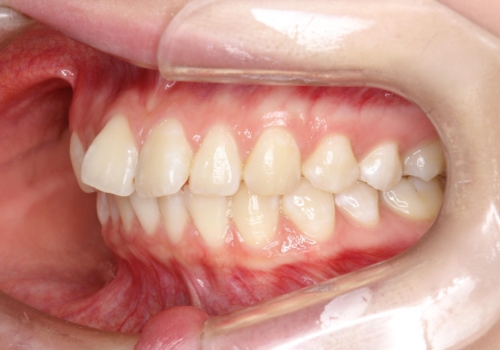

前歯のガタつきを治したい 翼状捻転マウスピース矯正

- 上顎前歯の突出、がたつき(翼状捻転)を主訴に来院されました。当院では総合歯科医療が可能であるため、矯正前処置として虫歯治療・歯周治療、親知らず抜歯を施行しました。その後、非抜歯かつ口元が出ないようなマウスピース治療を行いました。仕事柄、1日の装着時間が短くなってしまう時期もありましたが、患者様と相談しながら問題なく終了しています。